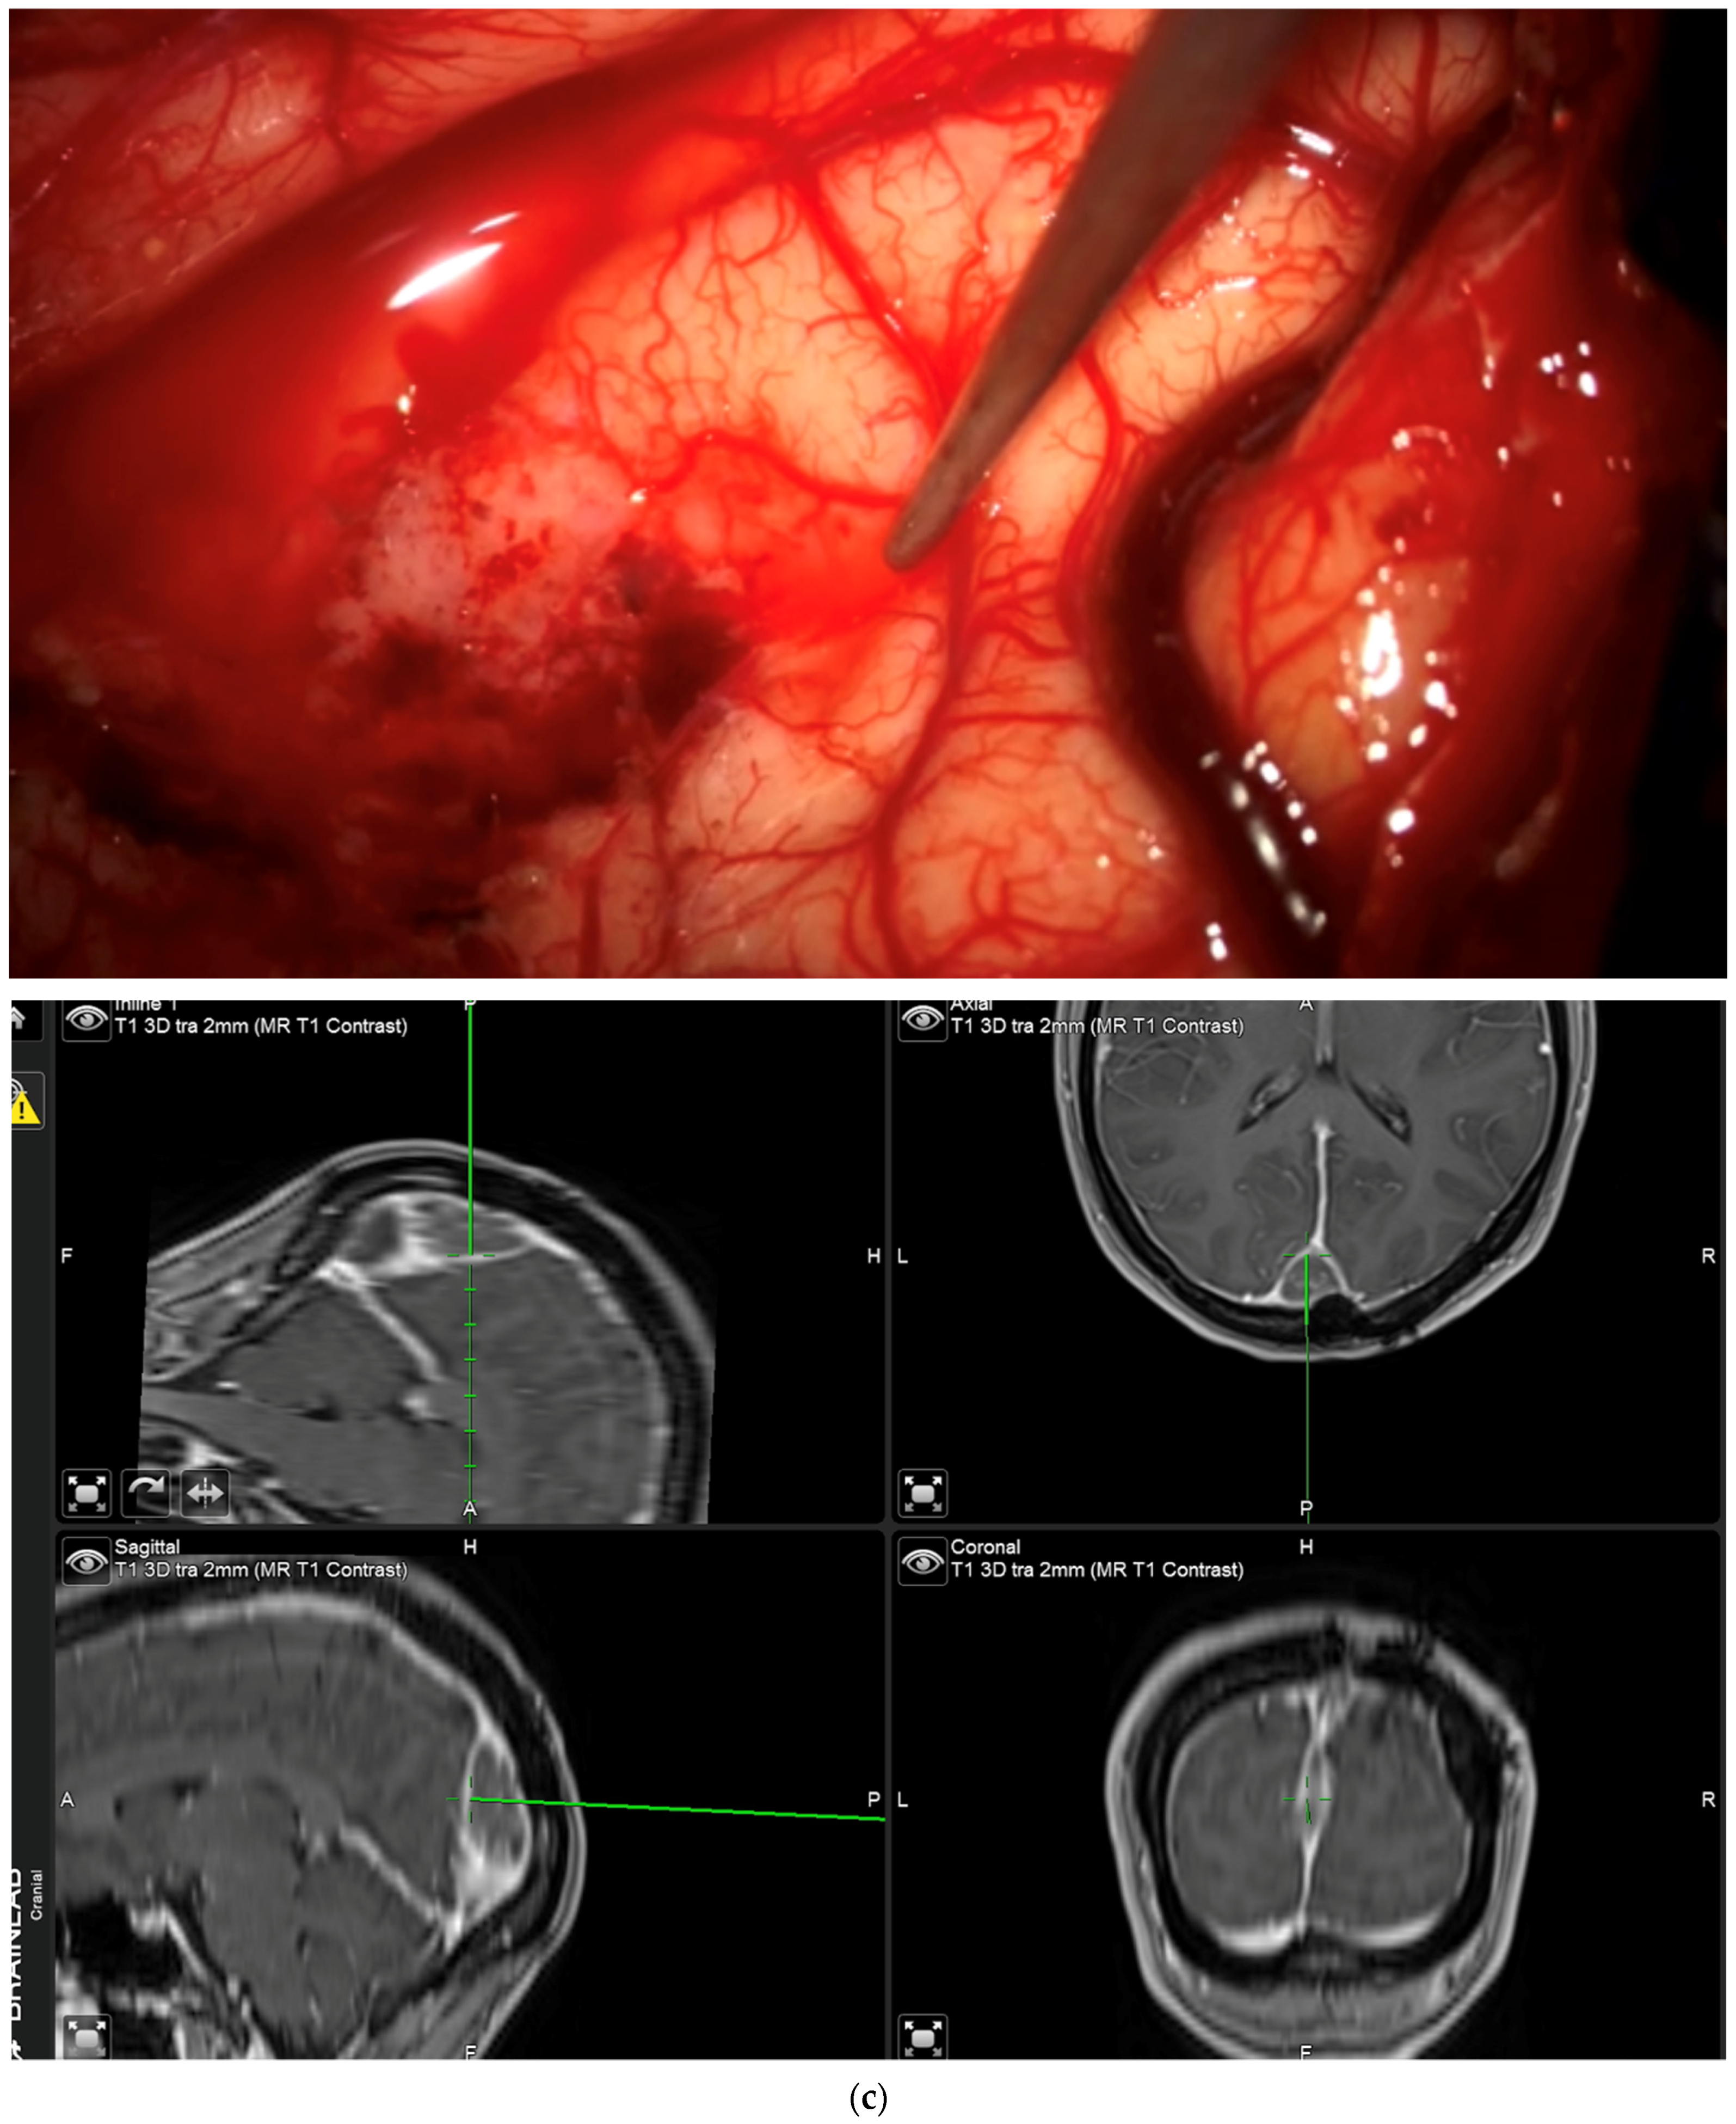

During the course of conventional white light surgery, the surgeon might encounter tissue which appears uncertain. From such “indeterminate” tissue the surgeon might require more information based on fluorescence. In such cases, the observation of fluorescence might lead to a change in surgical decision or surgical strategy. Such instances of indeterminate tissue may be found at the dural tail, in scar tissue with cases of recurrent meningioma, in the bone flap or at bony resection margins. In cases in which the surgeon requires more information based on fluorescence, the region in question is marked by the navigation pointer and a screenshot is taken. At this stage, the surgeon records his presumed diagnosis for the tissue area he or she desires more information for (“likely” or “unlikely” tumor) and his surgical decision based on his impression under white light (to resect or not to resect). The surgeon then switches to blue light, records whether he or she sees fluorescence, and states whether he or she plans to change surgical strategy based on fluorescence status. Under white light, the uncertain tissue is then biopsied for later histological evaluation. The entire process is recorded using the microscope’s video camera for later assessment by the review panel (Figure 2).

Biopsy from “indeterminate” tissue: In this study the surgeon might encounter tissue which appears uncertain (tumor or not, “indeterminate” tissue) during surgery and where fluorescence might be helpful. The location of a respective region is documented by the neuronavigation screenshot. The illumination is changed to blue light to determine whether the tissue fluoresces and a biopsy is then taken. The tissue interrogation procedure is recorded by video. (a) In this example a portion of the sagittal sinus infiltrated by meningioma has been resected. The anterior resection margin appears inconclusive as to whether it still contains tumor and is therefore regarded as being indeterminate. The location is documented using neuronavigation. The insert shows the pointer tip location marking the intended biopsy location. (b) No fluorescence is observed. The location is then biopsied. (c) Neuronavigation screenshot “A”: anterior; “P”: posterior; “L”: left; “R”: right).

After clearing a field from tumor under white light, with the surgeon no longer being able to identify residual tumor in that field of view, the surgeon has the possibility of switching to blue light to determine whether any pathological tissue can be identified based on fluorescence. If the surgeon finds residual fluorescing tissue after switching to blue light, this area is pointed out using the neuronavigation pointer (and a navigation screenshot is taken). A biopsy is taken from the exact same region after switching back to white light if this can be performed safely. This procedure is also recorded by video from beginning to end. Such interrogations might be performed at multiple stages of surgery, provided a particular area (field of view) has been cleared of tumor according to the impression of the surgeon under white light. The interrogation of an inconspicuous bone flap also constitutes an “end of surgery” scenario if the surgeon wants to rule out any tumor infiltration in the bone. If any fluorescent bone is encountered, then this is biopsied prior to drilling of the bone flap (Figure 3).

“End of surgery” biopsy: After clearing a field from tumor under white light, with the surgeon no longer being able to identify residual tumor in that field of view, the surgeon switches to blue light to determine whether any pathological tissue can be identified based on fluorescence. Any fluorescing tissue is pointed out using the neuronavigation pointer (and a navigation screenshot is taken). A biopsy is then taken collected. This procedure is recorded by video from beginning to end. (a) After dissecting tumor from the brain, the brain is considered free of tumor. (b) Various areas of fluorescence can be observed. The surgeon would then resect the fluorescing tissue shown. (c) Navigation pointer and corresponding screenshot (“F”: footwards; “H”: headward; “A”: anterior; “P”: posterior; “L”: left; “R”: right).